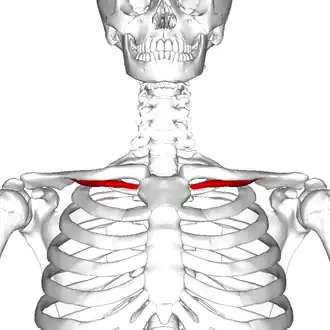

Subclavius muscle

Subclavius muscle (shown in red). | |

The subclavius is a small triangular muscle, placed between the clavicle and the first rib.[1] Along with the pectoralis major and pectoralis minor muscles, the subclavius muscle makes up the anterior axioappendicular muscles, also known as anterior wall of the axilla.[2]

Subclavius muscle (shown in red).

Subclavius muscle (shown in red). -